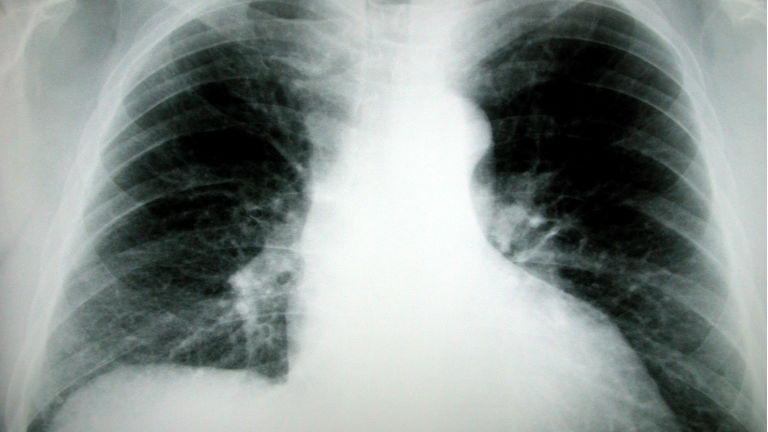

Nehéz diagnosztizálni az ismeretlen eredetű tüdőfibrózist. Az országban 150-200 betegről tudnak, de akár 2-3 ezren is lehetnek, csak nem tudnak róla. A betegség akár két évig is lappanghat. A tüdőfibrózis tünete lehet a nehézlégzés és a fáradékonyság, CT-vel és légzésfunkció-vizsgálattal lehet kimutatni.

A betegség lényege, hogy egy egyszerű fertőzés után a tüdő szövetei nem gyógyulnak meg. “Nem jó a regeneráció, nem alakul ki a normális tüdőstruktúra, hanem egy heges szövet képződik a helyén. Ez azt jelenti, hogy nem lesz olyan rugalmas a tüdő, nem olyan könnyű levegőt venni, nem lesz normális a gázcsere” – mondta el az RTL híradónak dr. Müller Veronika tüdőgyógyász.

Az ismeretlen eredetű tüdőfibrózisos betegek fele három éven belül meghal, gyógyszerrel tudják lassítani a folyamatot. Azt, hogy pontosan hogyan alakul ki a betegség, a mai napig nem tudják.